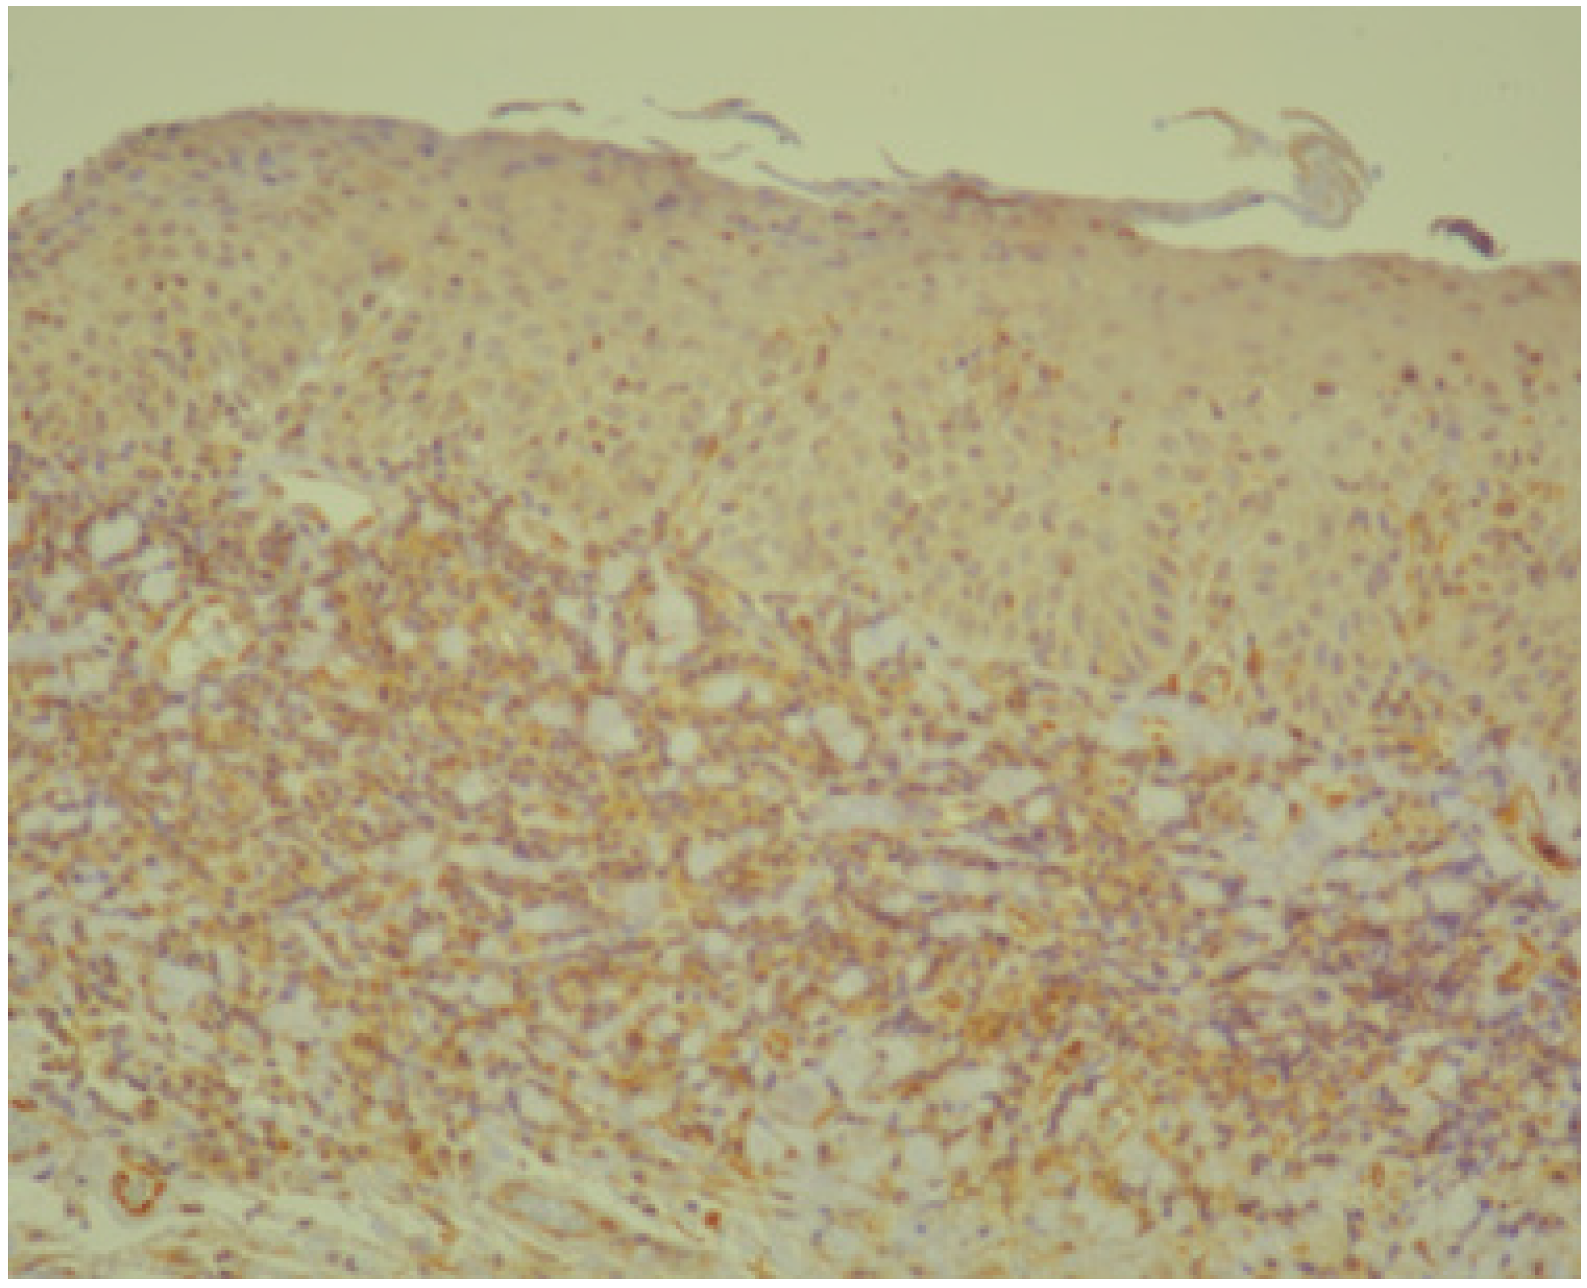

3.1. Histopathology and Immunohistochemistry